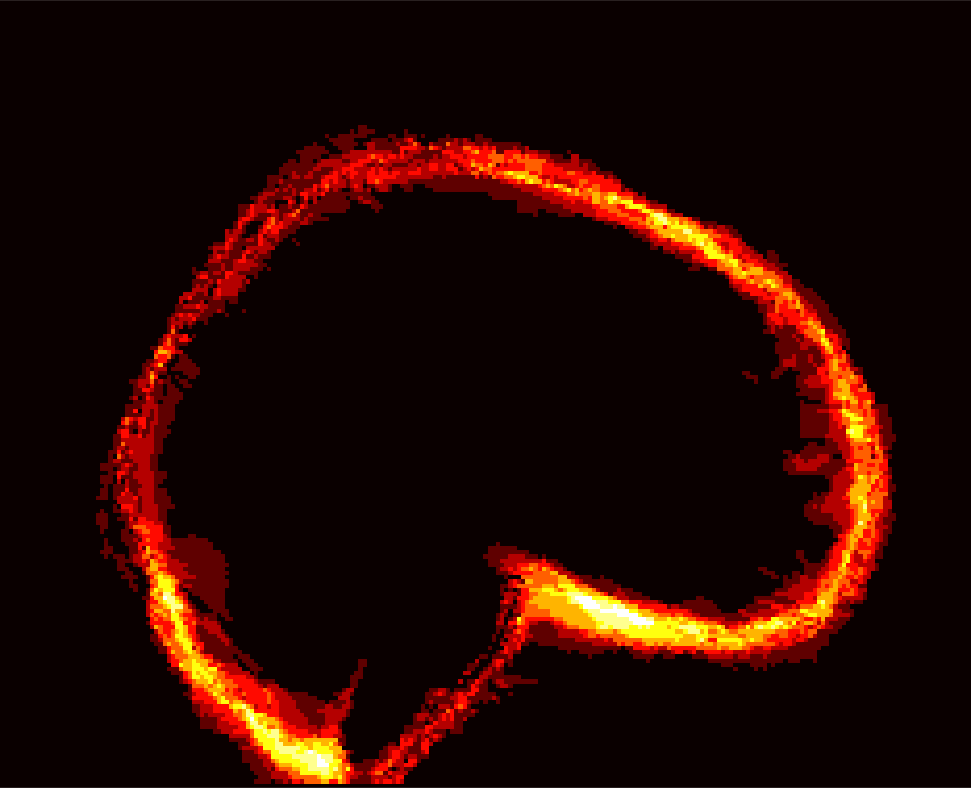

Fig. 9 (left) visualizes the average brain mask errors for IBSR and LPBA40. All images are first affinely registered to the atlas. Then we transform the gold-standard expert segmentations as well as the automatically obtained brain masks of the different methods to atlas space. We compare the segmentations by counting the average over- and under-segmentation errors over all cases at each voxel. This results in a visualization for areas of likely mis-segmentation. Our PCA model, ROBEX, BEaST (BEaST*) and BET perform well on these two datasets. Compareed to our model, ROBEX, BEaST (BEaST*) and BET show larger localized errors, e.g., at the boundary of the parietal lobe, the occipital lobe and the cerebellum. While MASS, BSE and CNN perform well on the LPBA40 dataset, they perform poorly on the IBSR dataset. This is in particular the case for the CNN approach.

Finally, Fig. 9 (right) shows the average segmentation errors on the BRATS and TBI datasets: our PCA method shows fewer errors than most other methods in these two abnormal datasets. MASS also shows few errors, while ROBEX, BEaST (BEaST*) and BET exhibit slightly larger errors at the boundary of the brain. CNN and BSE particularly show large errors for the BRATS dataset presumably again due to the coarse resolution of the BRATS data.

IBSR BRATS [Uncaptioned image]

PCA [Uncaptioned image] [Uncaptioned image] [Uncaptioned image] [Uncaptioned image] [Uncaptioned image] [Uncaptioned image]

ROBEX [Uncaptioned image] [Uncaptioned image] [Uncaptioned image] [Uncaptioned image] [Uncaptioned image] [Uncaptioned image]

BEaST* [Uncaptioned image] [Uncaptioned image] [Uncaptioned image] [Uncaptioned image] [Uncaptioned image] [Uncaptioned image]

MASS [Uncaptioned image] [Uncaptioned image] [Uncaptioned image] [Uncaptioned image] [Uncaptioned image] [Uncaptioned image]

BET [Uncaptioned image] [Uncaptioned image] [Uncaptioned image] [Uncaptioned image] [Uncaptioned image] [Uncaptioned image]

BSE [Uncaptioned image] [Uncaptioned image] [Uncaptioned image] [Uncaptioned image] [Uncaptioned image] [Uncaptioned image]

CNN [Uncaptioned image] [Uncaptioned image] [Uncaptioned image] [Uncaptioned image] [Uncaptioned image] [Uncaptioned image]

LPBA40 TBI

BEaST [Uncaptioned image] [Uncaptioned image] [Uncaptioned image] [Uncaptioned image] [Uncaptioned image] [Uncaptioned image]

Figure 9: Examples of 3D volumes of average errors for the normal IBSR and LPBA40 datasets, as well as for the pathological BRATS and TBI datasets. For IBSR/BRATS, we show results for BEaST*. Images and their brain masks are first affinely aligned to the atlas. At each location we then calculate the proportion of segmentation errors among all the segmented cases of a dataset (both over- and under-segmentation errors). Lower values are better (a value of 0 indicates perfect results over all images) and higher values indicate poorer performance (a value of 1 indicates failure on all cases). Clearly, BSE and CNN struggle with the BRATS dataset whereas our PCA method shows good performance across all datasets.